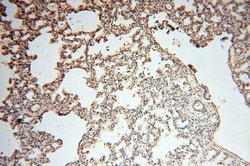

SYK Rabbit anti-Human, Mouse, Rat, Polyclonal, Proteintech

This gene encodes a member of the family of non-receptor type Tyr protein kinases. This protein is widely expressed in hematopoietic cells and is involved in coupling activated immunoreceptors to downstream signaling events that mediate diverse cellular responses, including proliferation, differentiation, and phagocytosis. It is thought to be a modulator of epithelial cell growth and a potential tumor suppressor in human breast carcinomas. Alternatively spliced transcript variants encoding different isoforms have been found for this gene.Specifications

| Immunohistochemistry (Paraffin) | |

| Human, Mouse, Rat | |